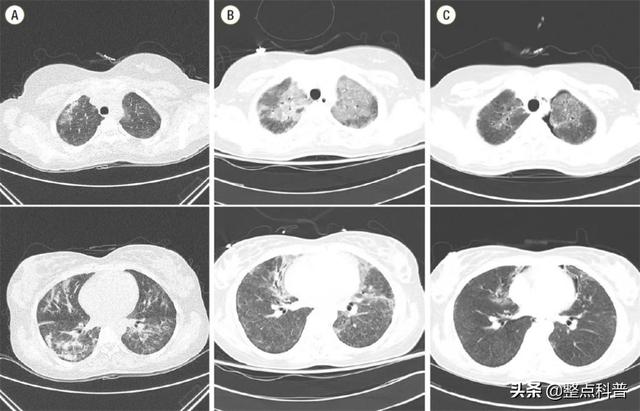

聚六亚甲基胍雾化后被人体吸入,很容易诱发不可逆的肺部损伤,出现咳嗽、呼吸困难和肺部弥漫性小叶中央毛玻璃样阴影、急性呼吸衰竭等症状,严重时还会导致死亡。

这说明在吸入状态下,肺部对聚六亚甲基胍的处理效率很低,长时间堆积很容易引起炎症或者肺部纤维化,这些都与因在加湿器中添加聚六亚甲基胍类消毒剂而死亡的人表现一致,更加证明了加湿器加消毒剂的危害性。